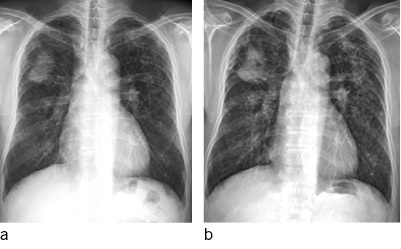

Mikronoduläre Verdichtungen (P-Schatten), mit geringer Streuung sind in den CT-Rekonstruktionen mit 1 mm Schichtdicke schwer von orthogonal getroffenen Gefäßen zu unterscheiden. Auch ein Lungenemphysem kann die Detektion gering gestreuter kleiner silikotischer Knötchen deutlich erschweren. Aus diesem Grund ist die Anfertigung von MIP-(Maximum Intensity Projection)-Rekonstruktionen mit 5-mm-Schichtdicke bei der Diagnostik nodulärer Erkrankungen obligatorisch um den Streuungsgrad sicher einschätzen zu können. Die Schichtdicke von 5 mm wurde gewählt, da die verfügbaren Referenzfilme zum großen Teil ebenfalls mit einer Schichtdicke von 5 mm dokumentiert wurden (  Abb. 4a–d ).